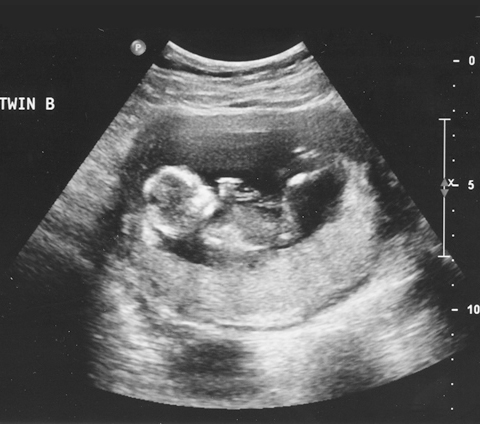

Se tienen convenios de colaboración para la realización de diversos estudios de gabinete con proveedores certificados para: